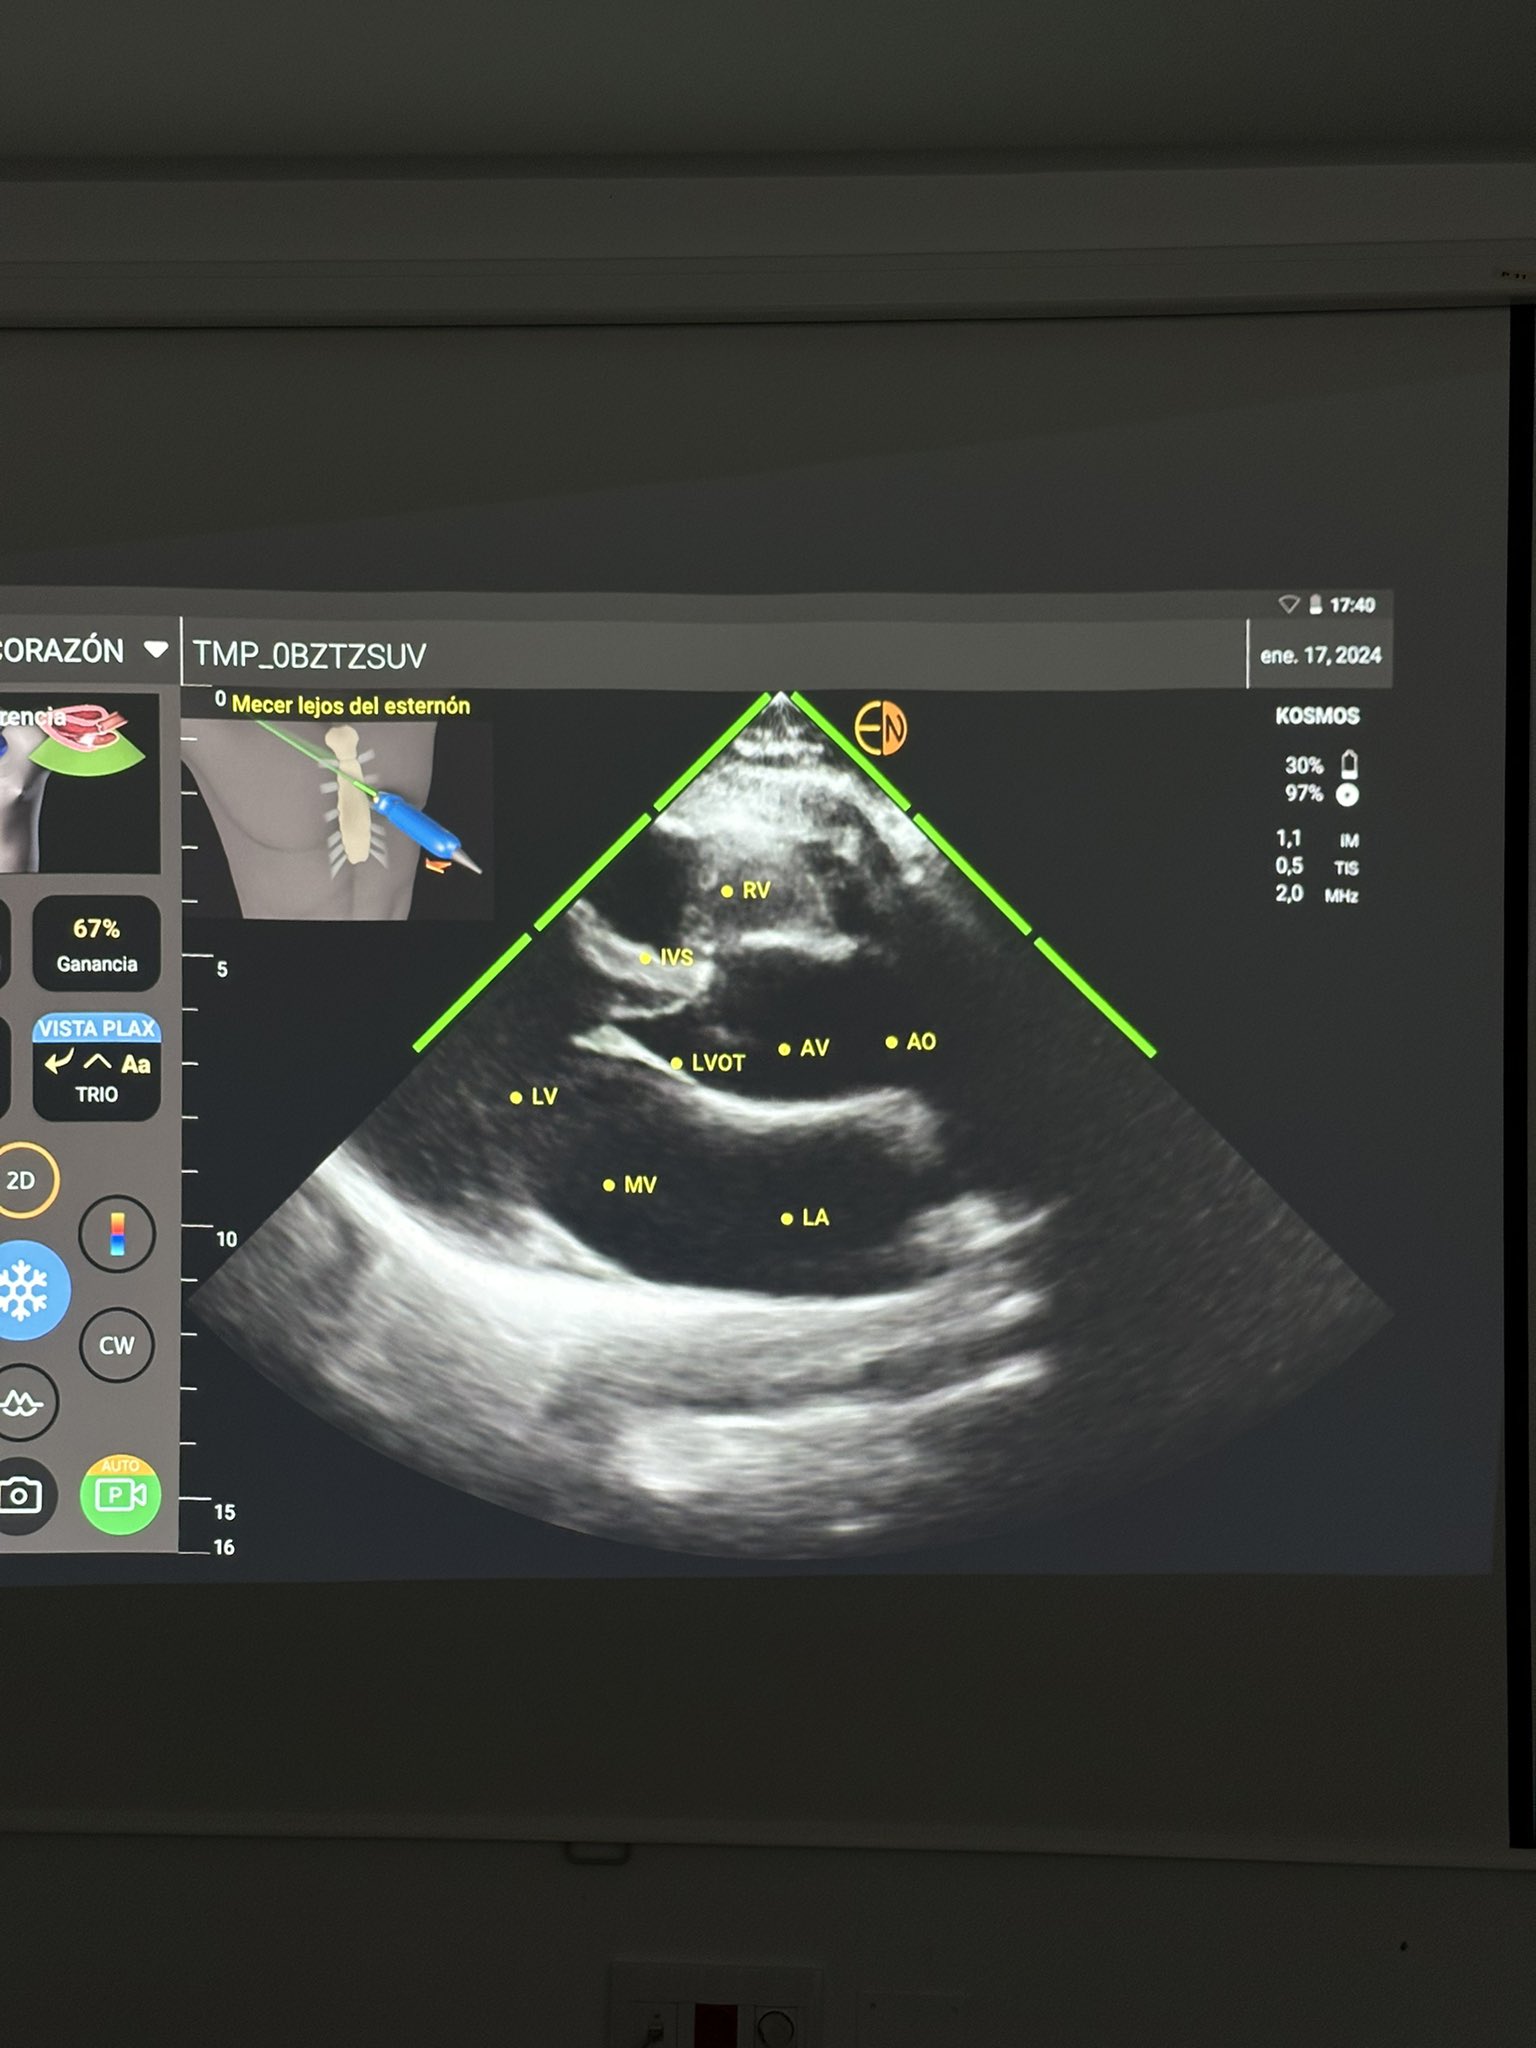

La Facultad de Medicina-AB junto al grupo de ecografía clínica URG-CHUA (bajo la dirección de nuestro profesor de Urgencias y Emergencias, Dr.Erick Mejías), desde el 18 de enero han iniciado la IMPLANTACIÓN del PROYECTO:

“POCUS EN PREGRADO: exploración física extendida mediante el ultrasonido (E-POCUS). Inspección, palpación, percusión, auscultación, insonación.

Objetivo: utilización de ecógrafos ultraportables con Inteligencia Artificial (IA) para facilitar el aprendizaje de nuestr@s estudiantes.